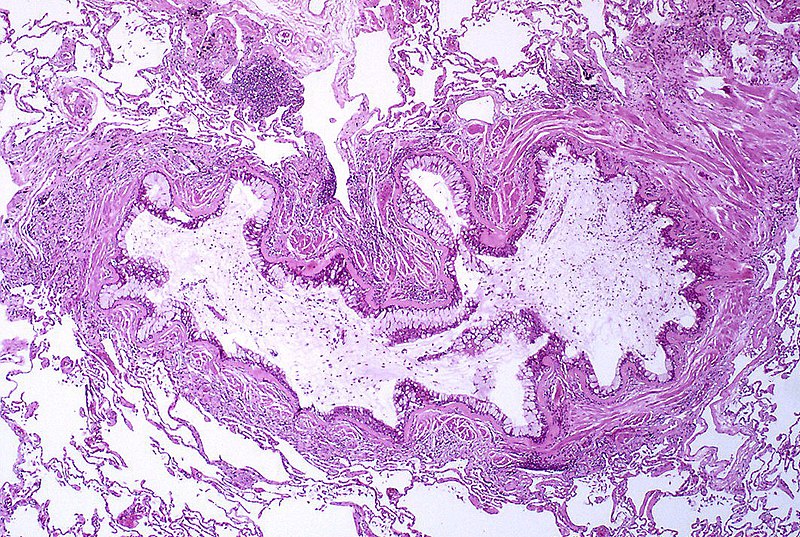

(A) Smoking-related interstitial fibrosis involving subpleural lung parenchyma (pleural surface is at the left) with centrilobular accentuation (arrow); (B) thickening of the alveolar septa by dense, eosinophilic, paucicellular collagen bundles. Pulmonary adenocarcinoma mutation profile in smokers with smoking-related interstitial fibrosis. Primiani A, Dias-Santagata D, Iafrate AJ, Kradin RL - International journal of chronic obstructive pulmonary disease (2014). Not Altered. CC.